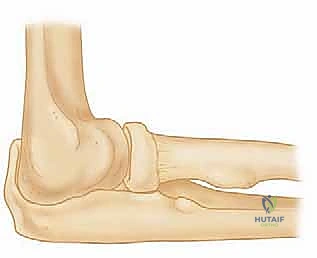

لكي ندرك تماماً حجم المشكلة وكيفية علاجها، يجب علينا الغوص في التشريح المعقد لمفصل الكوع. يتكون هذا المفصل من التقاء ثلاث عظام رئيسية:

1. عظم العضد (Humerus): عظمة الذراع العلوية.

2. عظم الزند (Ulna): العظمة الداخلية للساعد (جهة الإصبع الصغير).

3. عظم الكعبرة (Radius): العظمة الخارجية للساعد (جهة الإبهام).

تتصل هذه العظام معاً لتشكل ثلاثة مفاصل فرعية داخل كبسولة مفصلية واحدة. للحفاظ على هذه العظام في مكانها وتوفير الاستقرار الديناميكي أثناء الحركة، توجد شبكة معقدة من الأربطة. في الجهة الخارجية (الوحشية) من الكوع، يوجد ما يُعرف بـ مركب الرباط الجانبي الوحشي (LCL complex).

هذا المركب ليس مجرد خيط واحد، بل هو بنية تشريحية ثلاثية الأبعاد تتألف من أربعة مكونات رئيسية مترابطة: